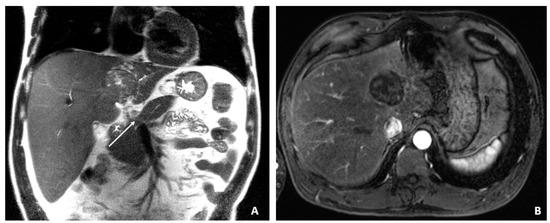

Figure 2.

Transarterial Chemoembolization (December 2009). (A) The selective left hepatic artery injection shows a blush of contrast corresponding to the hypervascular tumor (arrows). (B) An axial T1-weighted fat-suppressed portal-phase postcontrast MRI image 4 weeks following TACE shows lack of enhancement in the treated lesion with a small adjacent focus of necrosis (arrows).